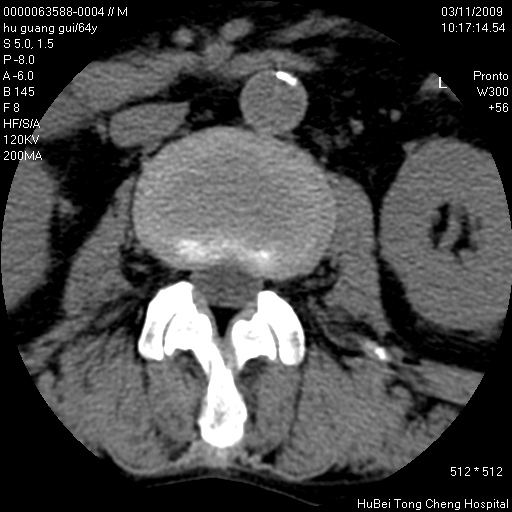

患者 男,64岁。腰痛十余天。(临床未提供其他病史)

临床诊断:腰痛原因待查(腰椎间盘突出症?)。

腰椎间盘ct轴位平扫(层厚5mm,层距4mm),图像如下:

腰椎退行性变,腰4—5椎间盘膨出。

右侧骶骨侧块骨侵蚀,骶髂关节骨性关节面破坏,并见软组织肿块,考虑骨转移瘤可能,进一步检查。

1.腰椎退行性变,腰4—5椎间盘膨出。

2.右侧骶骨侧块骨侵蚀,骶髂关节骨性关节面破坏,并见软组织肿块,考虑:脊索瘤,骨转移瘤可能,进一步检查。

1)腰椎退行性变,l4—5椎间盘膨出。2)骶骨右侧块骨转移瘤可能,3)水平骶椎。建议作一步检查。